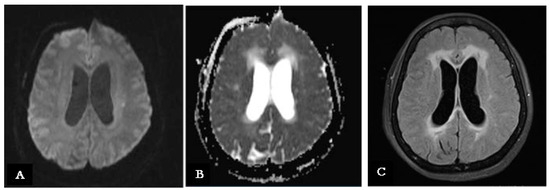

Several days later, a brain MRI with contrast revealed intense enhancement and thickening of the leptomeninges at the Sylvian fissure, skull base, and truncal and cervical regions. Nevertheless, additional hyperintense areas in diffusion-weighted sequences at the left corona radiata, corresponding to hyperintensity in FLAIR sequences, were found, suggesting a new small subacute ischemic lesion (Figure 3A–C).

Figure 3.

(A) A new MRI scan (performed during the stay in the infective disease ward) showing an hyperintensity signal on the left corona radiate on a DWI sequence, indicating a new ischemic lesion. (B) Same MRI brain scan on an ADC sequence showing a hypointense signal on the left corona radiate, indicating the same ischemic lesion on left corona radiate. (C) Same MRI brain scan on a FLAIR sequence showing a hyperintense signal on the left corona radiate, indicating the subacute evolution of the ischemic lesion.